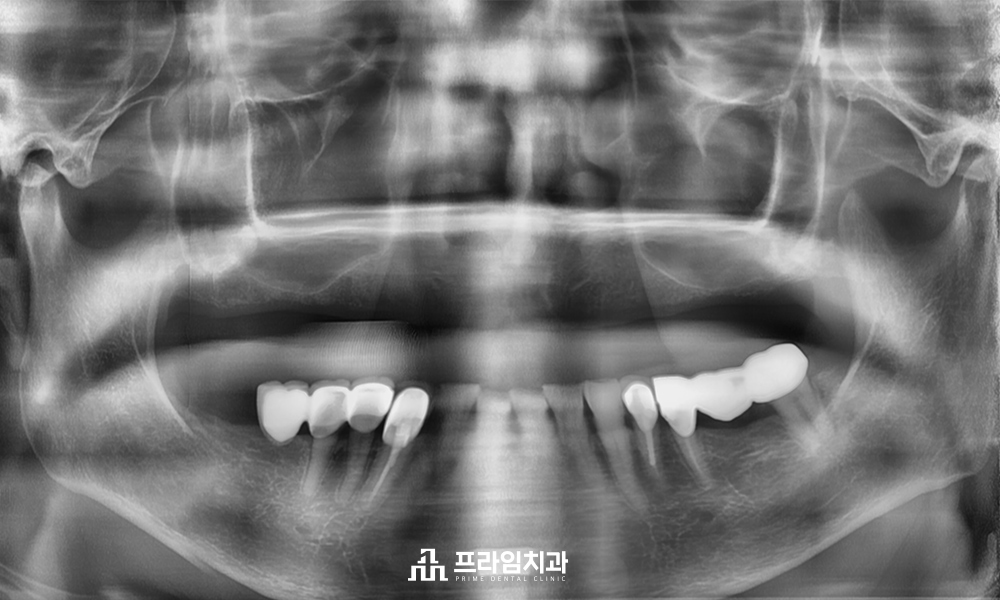

오늘은 상실하신 위쪽 치아 전체를 임플란트로 수복하신 환자분을 소개해 드리려고 하는데요. 오랜 기간 틀니를 사용하시다가 너무 불편하셔서 치료 상담을 위해 내원해 주셨습니다. 임플란트가 처음이셔서 걱정이 많으셨지만 충분한 상담 끝에 최소침습 임플란트를 통해 전체 식립을 진행하시기로 계획을 수립하였습니다.

아래쪽에 예후가 불량한 치아들까지 발치 후 최종 보철물까지 수복을 마친 모습입니다. 이는 치조골 폭이 좁거나 상태가 좋지 않더라도 식립 가능하여, 치조골 크기와 형태에 맞는 임플란트 선택이 가능합니다. 더불어 골이식이나 골 형성 등의 부가적인 수술도 줄여주고 감염이나 부러지는 등의 위험성이 감소하고 강한 보철 구조를 하고 있어 파절이나 나사가 풀리는 것과 같은 부작용이 발생할 우려가 적습니다.